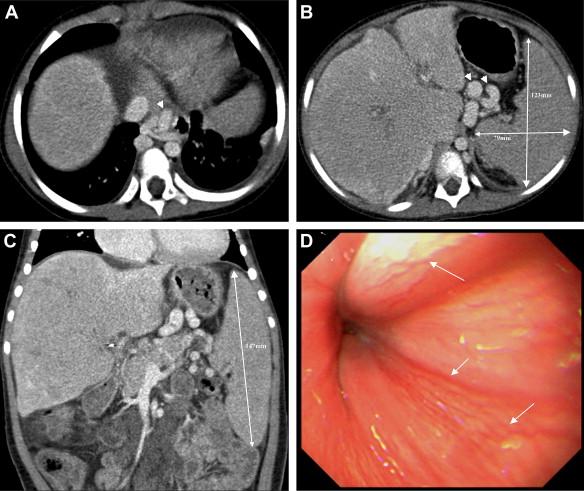

A 2476-day-old girl, with a body weight of 25kg and a height of 1.20m, has ...

A 2476-day-old girl, with a body weight of 25 kg and a height of 1.20 m, has recurrent cholangitis and fecal occult blood. (A) Computed tomography through the hepatic dome reveals engorged paraesophageal varices (arrowhead); (B) the perigastric varices are also engorged within the lesser sac (arrowheads). The transverse splenic length and width are 123 and 79 mm, respectively; (C) in the coronal plane through the splenic hilum, the splenic height is 147 mm. The transverse splenic length (mm)/body height (m)/platelet count (1000/mm3) is 1.69 and the splenic volume index (mm3)/body weight (kg)/platelet count (1000/mm3) ratio is 0.93; (D) there are several varices (arrows) disclosed by esophagogastroduodenoscopy on the lower esophageal wall.